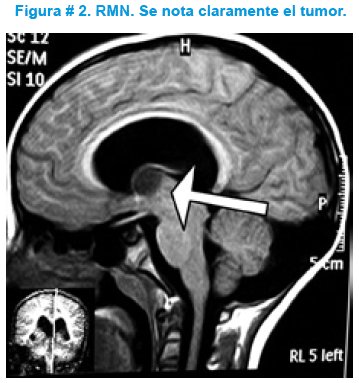

Aproximadamente dos años después presentó 8 días de cefalea holocraneana, de tipo opresivo, no irradiado, vómitos en proyectil, que no cedieron al tratamiento. Se solicitó TAC de cráneo que demostró hidrocefalia aguda y disfunción valvular. Llamó la atención la presencia de una imagen iso-densa sobre el III ventrículo, por ello se solicitó resonancia magnética nuclear de cerebro que mostró la presencia de un tumor en región frontal del ventrículo lateral a nivel septal, de bordes definidos, circular, que separaba ambas hojas del septum pellucidum y obliteraba los agujeros de Monro. Ver figura # 2.